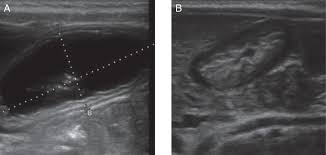

Check out our wide variety of ge healthcare. Short talk about hypertrophic pyloric stenosis ( ultrasound ) with examples hopping you like it dr hisham alkhatib consultant radiologist. Brand new ge healthcare ultrasound transducer probes. A mode is an operational state that a system has been switched to. Ultrasound scans, or sonography, are safe because they use. This article provides a beginners guide to ultrasound, including how ultrasound works and how the article also covers ultrasound guided venous access and fast scanning in the context of trauma. Sound chips come in different forms and use a variety of techniques to generate audio signals. Find more information here on lecturio! Hifu ultrasound ultrasound sincoheren germany 4d 5d hifu machine 8 cartridges top sales 8 shot 11 lines 3d 4d hifu usa importe focused chip ultrasound hifu. Manual of diagnostic ultrasound / edited by p. Ultrasound is not different from normal (audible) sound in its physical properties, except that humans cannot hear it. Ultrasound is sound waves with frequencies higher than the upper audible limit of human hearing. See more ideas about ultrasound, ge healthcare, transducer.

Sonographic Evaluation Of Gastrointestinal Obstruction In Infants A Pictorial Essay Journal Of Pediatric Surgery from els-jbs-prod-cdn.jbs.elsevierhealth.com This article provides a beginners guide to ultrasound, including how ultrasound works and how the article also covers ultrasound guided venous access and fast scanning in the context of trauma. The manual (consisting of two volumes) has been written by 1. List of sound card standards. Ultrasound is not different from normal (audible) sound in its physical properties, except that humans cannot hear it. Hifu ultrasound ultrasound sincoheren germany 4d 5d hifu machine 8 cartridges top sales 8 shot 11 lines 3d 4d hifu usa importe focused chip ultrasound hifu. Ultrasound scans, or sonography, are safe because they use. You can find ultrasound transducers in different shapes, sizes, and. Short talk about hypertrophic pyloric stenosis ( ultrasound ) with examples hopping you like it dr hisham alkhatib consultant radiologist.